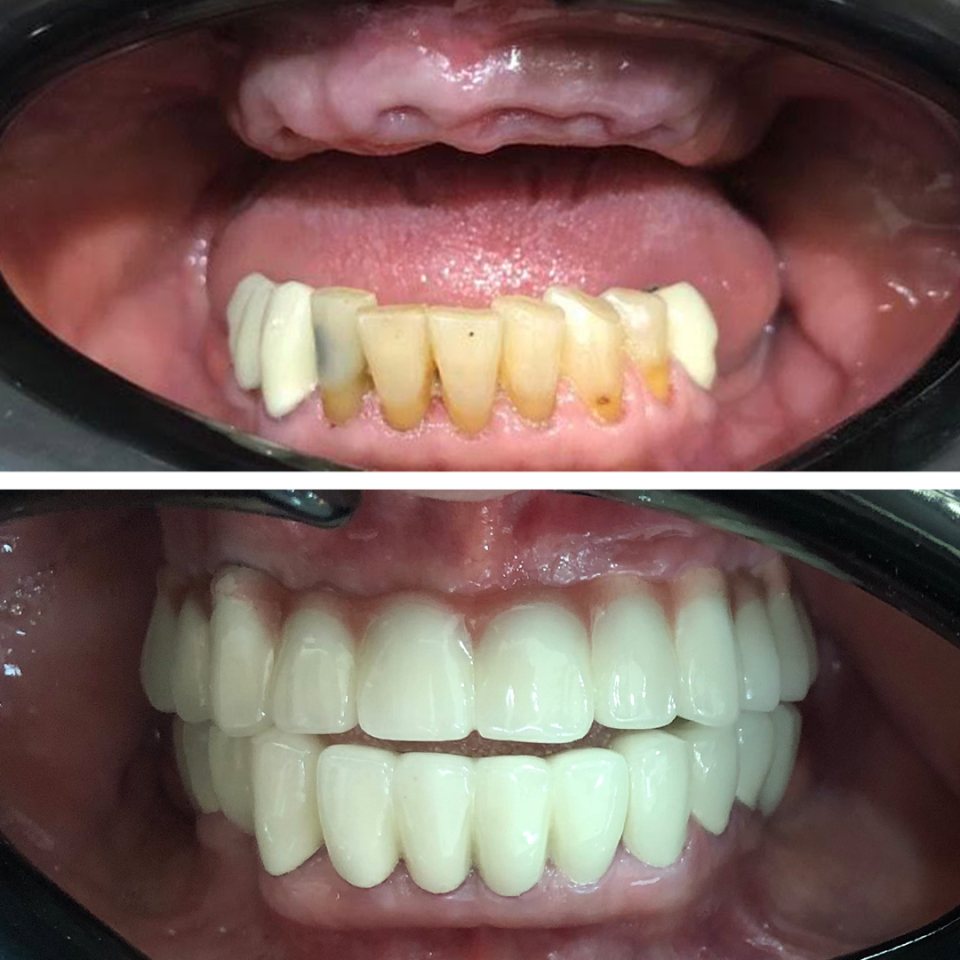

Smile Dental Clinic Turkey Gallery

Our Gallery and Happy Patients

Let’s make a change and put a perfect smile on your face with our dental clinic in Antalya/TURKEY.